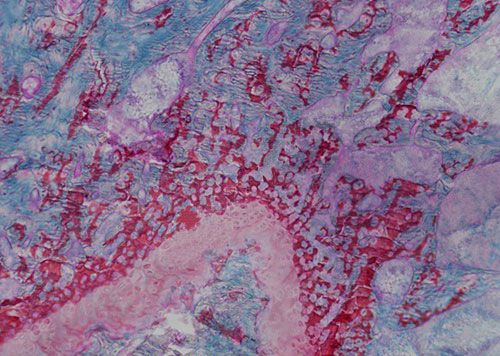

• 未脫鈣骨番紅固綠染色

未脫鈣骨番紅固綠染色

番紅O(Safranin O)-固綠(Fast Green),簡稱番紅固綠,是一種經典的軟骨染色方法,因可以直觀反映關節軟骨、軟骨下骨及骨組織結構而備受青睞。未脫鈣骨硬組織切片經番紅固綠染色后,軟骨呈紅色, 成骨呈綠色。

未脫鈣大鼠骨番紅固綠染色

切片脫塑-固綠染色-番紅染色-脫水封片-顯微鏡鏡檢